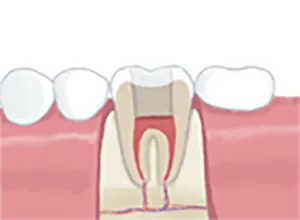

• 土台の装着

5土台の装着

歯の土台となる部分を装着し、歯を整えていきます。

• 被せ物の装着

6被せ物の装着

歯科素材での被せを装着して完成です。